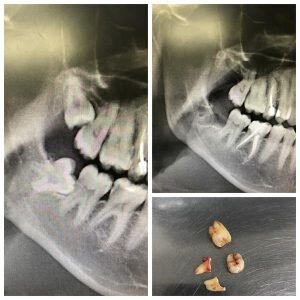

Начну с того, что НИКАКОЙ, подчеркиваю, НИКАКОЙ необходимости удалять такие зубы

или, например, такие:

в челюстно-лицевом стационаре НЕТ! Об этом я писал в ЭТОЙ статье. Запомните раз и навсегда, что челюстно-лицевой хирург не Дэвид Блейн или Амаяк Акопян и он не отодвинет нерв от зуба. В этом случае, даже если «дунуть», чуда не произойдет как ни крути. Следовательно, нет разницы, ГДЕ вы удаляете зуб. Важно, КТО это будет делать. Ведь для того, чтобы онемение появилось, достаточно элементарного давления, которое оказывает корень зуба на нерв при его «раскачивании». Конечно, есть виртуозы, которые перебивают нерв бором или разрывают его в процессе удаления. Такие товарищи ещё называют его «лицевым нервом». Видимо, потому что губа и подбородок – это часть лица. Хочется верить, что таких специалистов единицы, потому как лицевой нерв проходит несколько в другом месте. Как минимум, существует компьютерная томография, которая позволяет понять, где и как именно этот нерв (а имя ему «нижнечелюстной»/«нижний альвеолярный нерв»), проходит. На схеме цифра 1:

Даже если онемение обусловлено не отеком, а «повреждением» нерва, нет причин для паники. В максимально короткие сроки назначаются препараты комплекса витаминов группы B. Как правило, на следующий день после манипуляции. Почему на следующий? Чтобы можно было сказать наверняка – парестезия это или же не до конца отошла анестезия. Обычно это «мильгамма» или «нейромультвит». Они есть как в таблетках, так и в уколах. В том случае, если дома у пациента есть кому сделать укол или же передо мной человек на опыте, то на две недели я назначаю именно инъекции, после еще на две – таблетки. Если же такой возможности нет, то можно обойтись таблетками в течение всего месяца. Зачастую этого достаточно. Иногда назначают физиотерапию, но лично я отношусь к этому скептически. Да простят меня физиотерапевты. Не стоит забывать, что самый важный фактор – время. Процесс восстановления достаточно длительный. Если в первый месяц заметны улучшения, хоть и не явные, то всё обязательно восстановится. Звоночком может послужить лишь стабильное онемение, которое никак не меняется в лучшую сторону в течение нескольких месяцев. Но и в этом случае паниковать не стоит. Процесс восстановления при серьезном повреждении может доходить в среднем до полугода. Несколько лет назад у меня на приеме был пациент по острой боли с восьмеркой, в области которой развилась киста:

Красным отмечена киста.

Оранжевым отмечен канал, в котором проходит нижнечелюстной нерв.

Ещё до удаления пациент отмечал изменение чувствительности в области подбородка. Разъяснив все риски, я сказал, что онемение будет практически наверняка, но что поделаешь, острое состояние – зуб необходимо удалять:

Полное восстановление чувствительности у молодого человека заняло около 7 месяцев. И такое бывает (в седьмом зубе были пролечены каналы и установлена пломба)

Ниже снимок спустя примерно год после удаления: